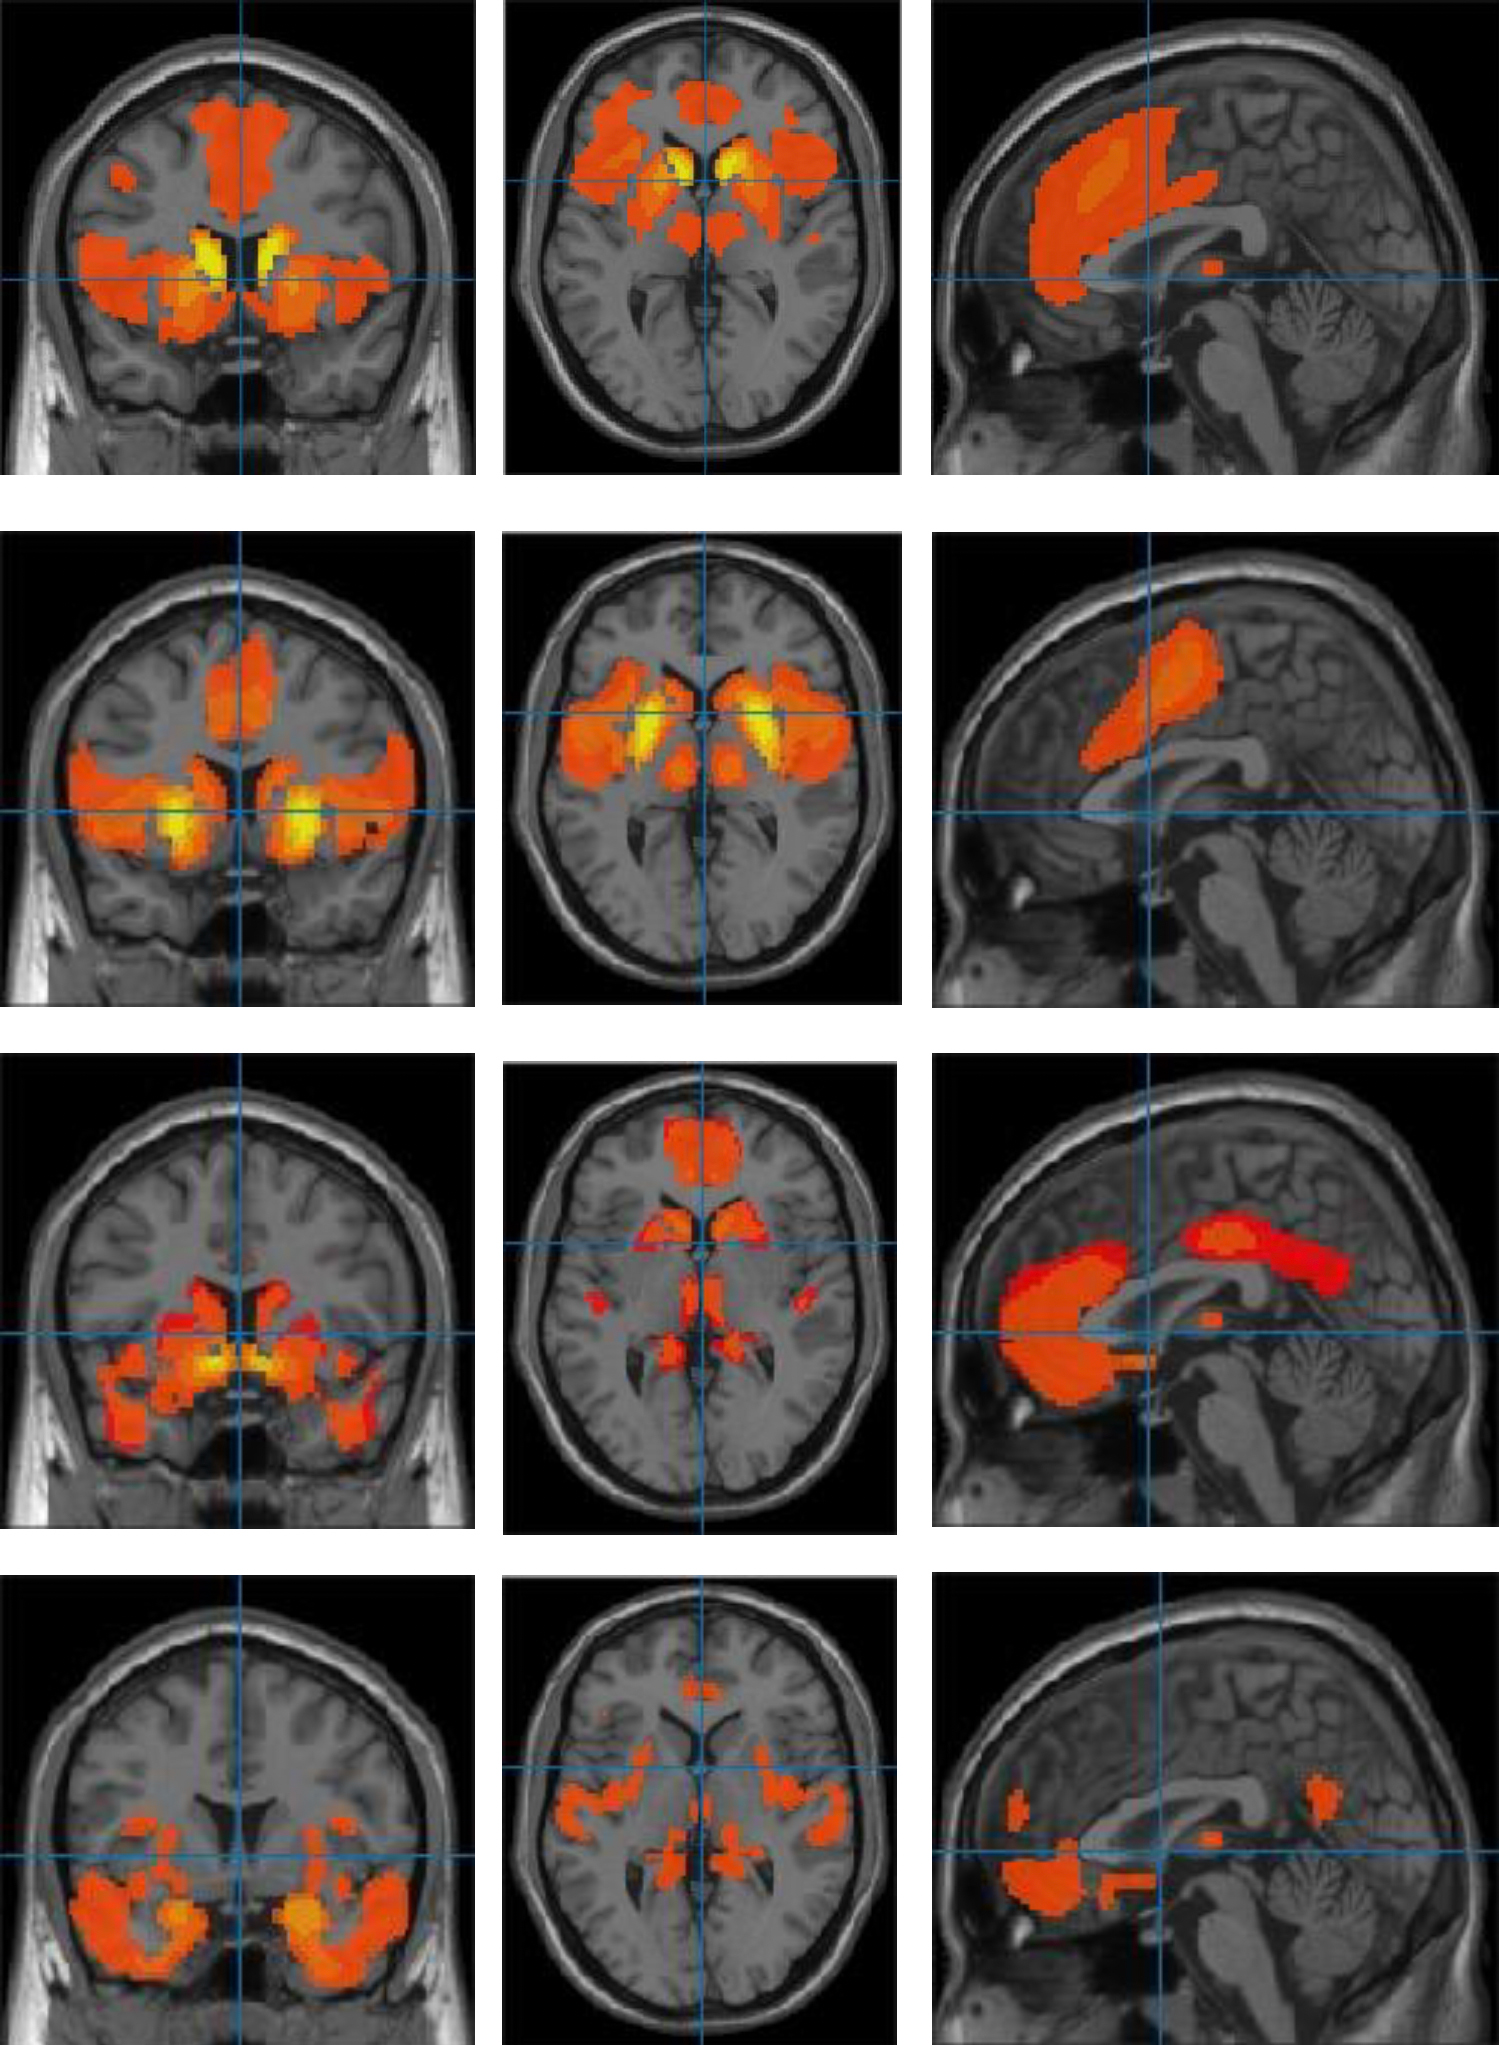

In a University of Zurich study, 44 volunteers received non-invasive electrical stimulation to the frontal and parietal brain areas while deciding how to split money. When stimulated simultaneously, participants showed a modest but consistent increase in generosity toward an anonymous partner, though effects were short-lived and would require repeated sessions for longer-term change. Researchers say this demonstrates a causal link between these networks and altruistic choices and could inform treatment of social-behavior disorders, with ethical safeguards in place.